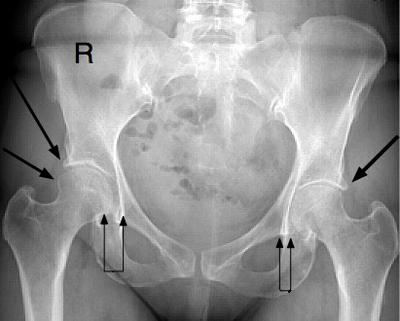

Unfortunately, I have lost my battle and will be getting a hip replacement in two weeks, but to know that all the times doctors did not understand and through in my endless search to find someone as smart as my chiropractor from many years ago there is someone out there who can succinctly and clearly explain the years of symptoms and pain.